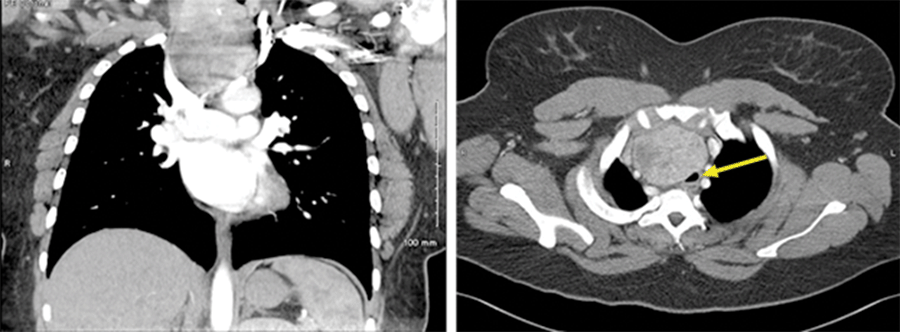

The patient was a 35-year-old female with a medical history significant for obesity (BMI 43.52 kg/m2), asthma, and gastroesophageal reflux (GERD). As part of an evaluation for possible sarcoidosis, a computed tomography (CT) scan was performed and revealed a large, retrosternal thyroid goiter (Figure 1), prompting a referral to an endocrine surgeon for evaluation.

Figure 1. CT Image Demonstrating Substernal Involvement of Thyroid Goiter and Moderate Tracheal Compression. Published With Permission

Cervical ultrasonography revealed a 5.6 cm left lobe and an enlarged right thyroid lobe measuring 9.4 cm at its largest dimension with an 8.9 cm nodule (Figure 2). On CT imaging, the right thyroid lobe measured 6.0 × 7.0 × 8.0 cm, with 6 cm of retrosternal extension reported. The trachea was deviated to the left and compressed to 9 mm in diameter. The thyroid imaging reporting and data system (TI-RADS) score for the nodule was three, based on composition and echogenicity.1 Combined with its large size, a fine needle aspiration (FNA) biopsy was performed. Cytology was consistent with a benign nodule (Bethesda II).2 It was discussed that given the extensive mediastinal extension of the goiter and the fact that the base was wider than the area at the thoracic inlet, it was possible that a sternotomy would be required at the time of thyroidectomy. Based on risks (likelihood of necessary sternotomy) and benefits, the decision was made to postpone surgery until after the delivery of her baby.